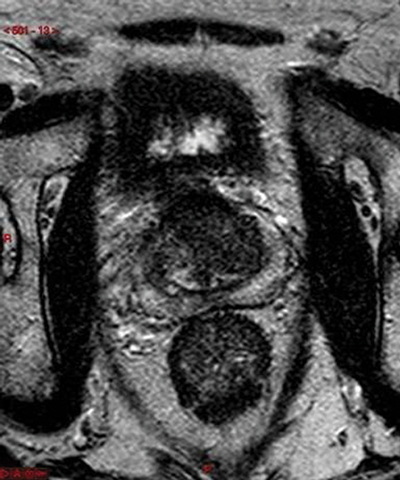

T4 disease is spread of tumour into adjacent tissues other than seminal vesicles, such as bladder, rectum or pelvic side-wall. Invasion is demonstrated by loss of the fat plane between the tumour and the structure, or in cases of more aggressive disease, visualisation of tumour within that structure (Figure 7) [3]. The sagittal T2W sequence is particularly useful at identifying bladder and rectal invasion [4].

Figure 7: Axial T2 showing extensive prostate tumour invading the bladder and bilateral iliac lymph nodes.

Lymphadenopathy and distant metastases

Large FOV axial T1W images are most useful for identifying local adenopathy. Criteria similar to those used in CT staging are often applied to MR to define clinically significant nodal involvement. Enlarged, spherical lymph nodes measuring at least 1cm in short axis dimension with loss of normal internal architecture are considered significant (Figure 7). Large FOV multiplanar T2W images of the abdomen and pelvis may be acquired to look for distant nodal disease or distant organ involvement. This is used in conjunction with CT, particularly in stage III or IV disease and when considering pre-treatment lymph node sampling [7]. T1 images should be evaluated to assess for bone metastases and will be seen as low signal intensity compared with the normal high signal marrow fat.